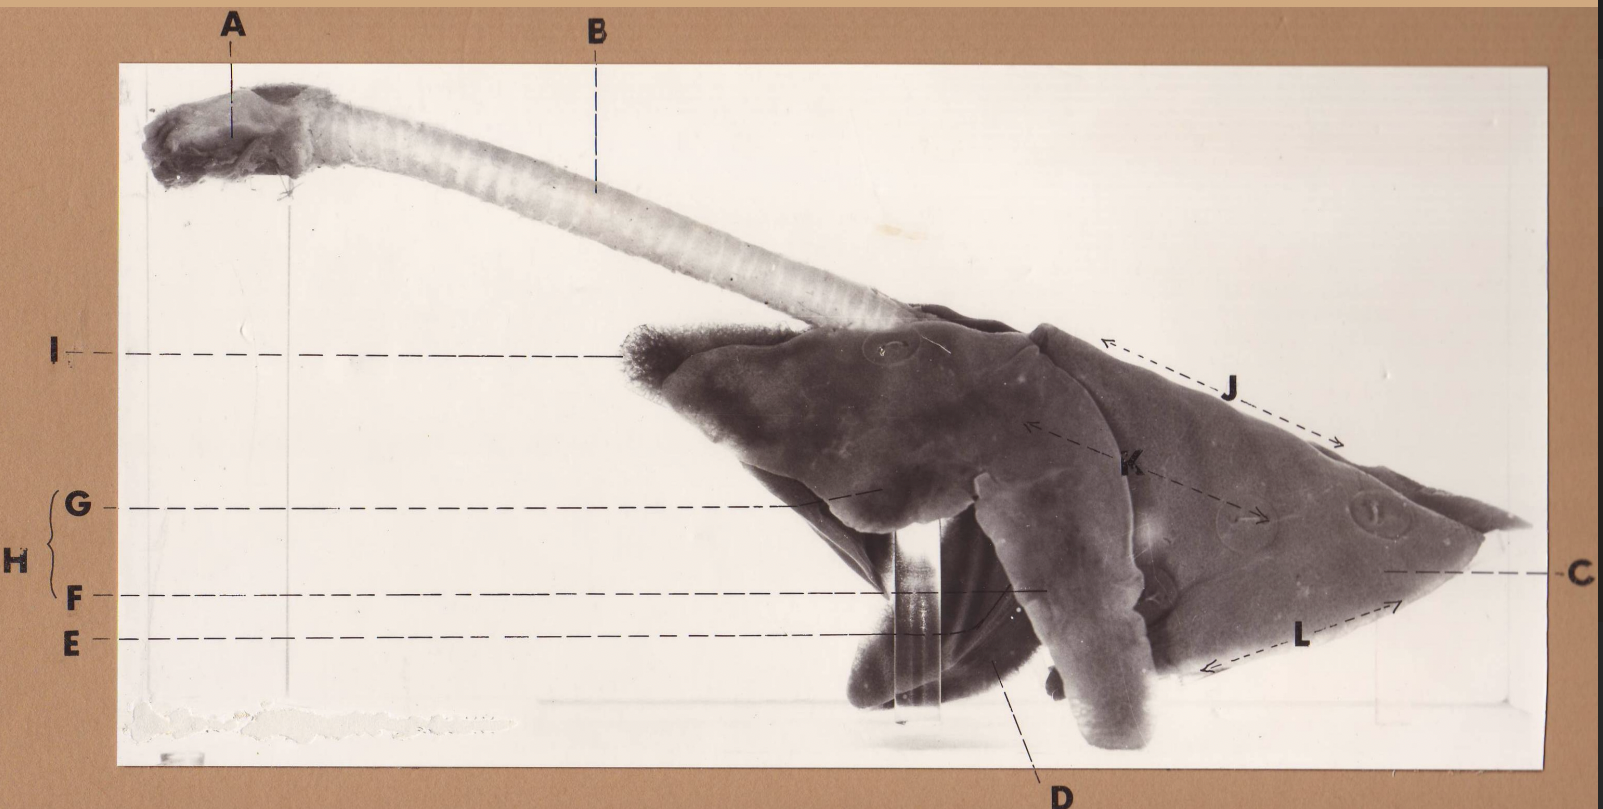

A

(cat larynx/trachea/lungs, L lateral)

larynx

B

(cat larynx/trachea/lungs, L lateral)

trachea

C

(cat larynx/trachea/lungs, L lateral)

caudal lobe

D

(cat larynx/trachea/lungs, L lateral)

middle lobe

E

(cat larynx/trachea/lungs, L lateral)

cardiac notch

F

(cat larynx/trachea/lungs, L lateral)

caudal segment, cranial lobe

G

(cat larynx/trachea/lungs, L lateral)

cranial segment, cranial lobe

H

(cat larynx/trachea/lungs, L lateral)

cranial lobe

I

(cat larynx/trachea/lungs, L lateral)

apex

J

(cat larynx/trachea/lungs, L lateral)

dorsal border

K

(cat larynx/trachea/lungs, L lateral)

costal surface

L

(cat larynx/trachea/lungs, L lateral)

basal border